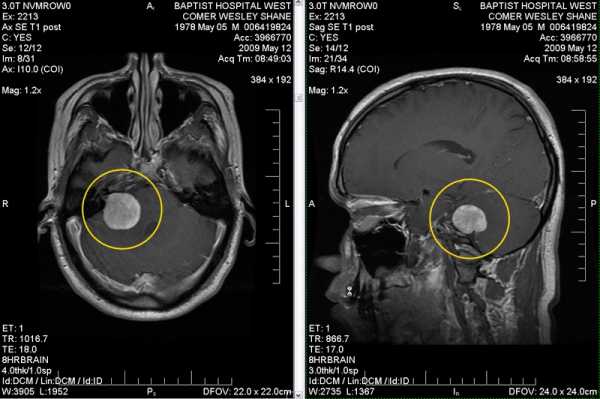

Диагностика опухолей головного мозга основана на визуализации патологического образования. Для этого применяется компьютерная или магниторезонансная томография. Предпочтительнее применение МРТ ввиду большей его информативности при диагностике данной патологии.

На томографическом снимке определяется локализация опухоли и ее отношение к окружающим структурам мозга. Так же, для дифференциальной диагностики вида опухоли и определения степени злокачественности, проводится тонкоигольная биопсия.

Все эти симптомы могут развиваться постепенно, порой настолько медленно, что ни сам больной, ни его родственники не успевают заметить изменений. Хотя бывает и бурное, резкое изменение состояния человека из-за бурного роста опухоли. Такие симптомы, как головокружение, проблемы с речью, нарушения координации могут быть ошибочно приняты за симптомы инсульта. Поэтому очень важна точная диагностика. Достоверные данные о наличии или отсутствии опухоли сегодня получить не трудно. Для этого достаточно сделать магнитно-резонансную томографию (МРТ).

Основной метод лечения #8212; операция по удалению или разрушению опухоли. Современные технические средства позволяют разрушить опухоль в мозге, даже не вскрывая кости черепа. Однако это не всегда возможно и не всегда оправдано. Поэтому вопрос о лечении решается индивидуально в каждом случае, обязательно учитываются результаты полного комплекса обследований: МРТ, анализ крови, гистологический анализ опухоли, если это возможно.